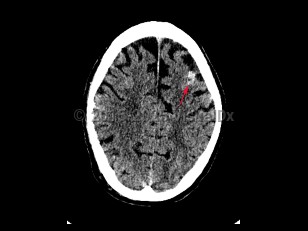

Brain abscessBrain abscess